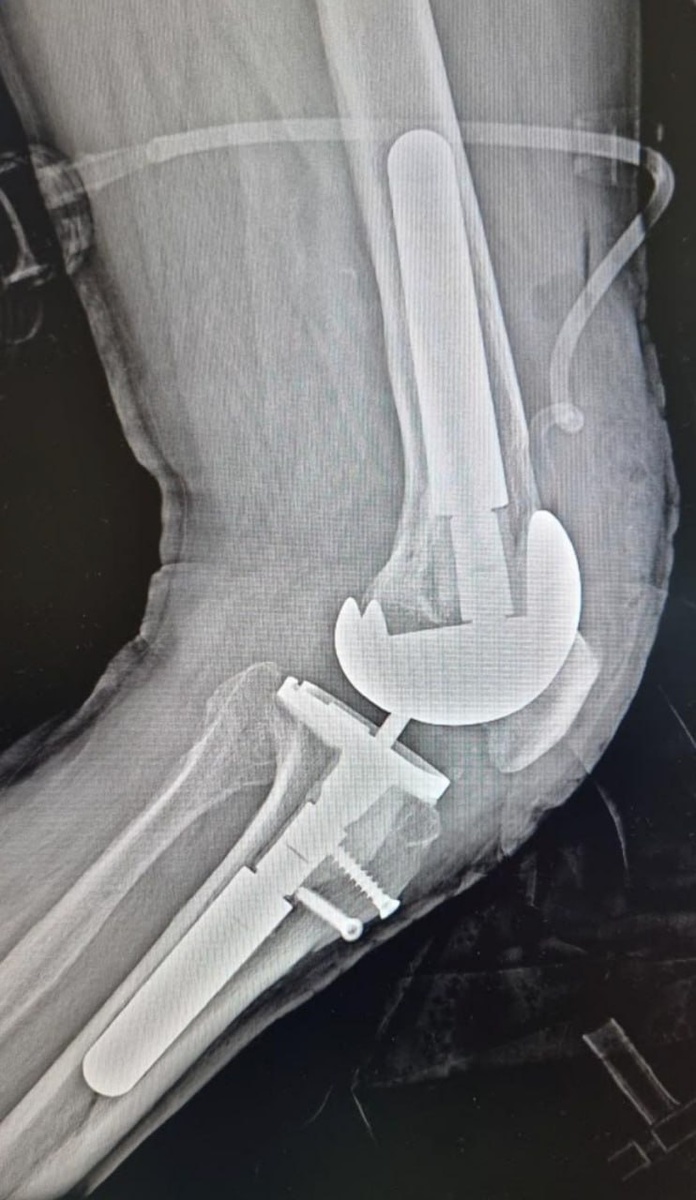

Врачи «Пироговки» впервые провели ревизионное эндопротезирование коленного сустава

Травматологи-ортопеды ММЦ имени Н. И. Пирогова ФМБА России впервые провели операцию по ревизионному эндопротезированию коленного сустава. Пациент – 75-летний житель города Апатиты. Заведующий отделением травматологии и ортопедии Сергей Боженко объяснил, что «ревизия» - это операция по замене установленного ранее протеза сустава на новый. При этом возможна как полная переустановка имплантатов, так и частичная замена изношенных компонентов. Сама по себе операция очень сложная, тяжёлая, с длительным восстановительным периодом. Нужно убрать старый протез и все его компоненты и установить новый. Сложность в том, что при удалении протеза всегда возникает дефицит костной ткани, который нужно заполнить специальными компонентами Он подчеркнул, что новые операции стали возможны благодаря тому, что врачи многопрофильного центра постоянно повышают свою квалификацию, а техническое оснащение больницы улучшается с каждым годом. С 2025 года мы успешно проводим ревизионное эндопротезирование тазобе

Травматологи-ортопеды ММЦ имени Н. И. Пирогова ФМБА России впервые провели операцию по ревизионному эндопротезированию коленного сустава. Пациент – 75-летний житель города Апатиты.

Заведующий отделением травматологии и ортопедии Сергей Боженко объяснил, что «ревизия» - это операция по замене установленного ранее протеза сустава на новый. При этом возможна как полная переустановка имплантатов, так и частичная замена изношенных компонентов.

Сама по себе операция очень сложная, тяжёлая, с длительным восстановительным периодом. Нужно убрать старый протез и все его компоненты и установить новый. Сложность в том, что при удалении протеза всегда возникает дефицит костной ткани, который нужно заполнить специальными компонентами